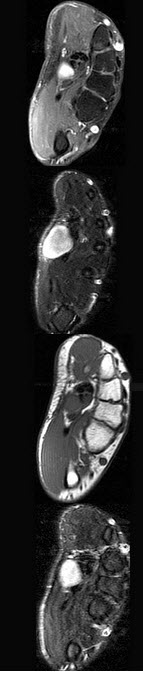

男,35岁,掌底有肿块,结合图像,最可能的诊断是()

A .囊肿

B .脓肿

C .神经纤维瘤

D .神经鞘瘤

E .未见异常